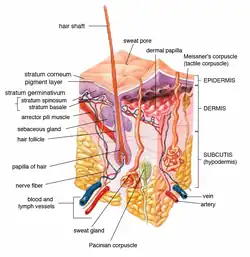

Poromas are rare, benign, cutaneous adnexal tumors.[1] Cutaneous adnexal tumors are a group of skin tumors consisting of tissues that have differentiated (i.e. matured from stem cells) towards one or more of the four primary adnexal structures found in normal skin: hair follicles, sebaceous sweat glands, apocrine sweat glands, and eccrine sweat glands.[2] Poromas are eccrine or apocrine sweat gland tumors derived from the cells in the terminal portion of these glands' ducts.[3] This part of the sweat gland duct is termed the acrosyringium and had led to grouping poromas in the acrospiroma class of skin tumors (syringofibroadenomas and syringoacanthomas are classified as acrospiromas).[3][4][5][6] Here, poromas are regarded as distinct sweat gland tumors that differ from other sweat gland tumors by their characteristic clinical presentations, microscopic histopathology, and the genetic mutations that their neoplastic cells have recently been found to carry.[7]

As currently viewed, there are 4 poroma variants based on their predominant cell types and extent of their tumor tissues presence in the epidermis and dermis: 1) Hidroacanthoma simplex poromas are confined to the epidermis, i.e. uppermost layer of the skin. 2) Dermal duct poromas are confined to the dermis, i.e. layer of skin between the epidermis and subcutaneous tissues.[8] 3) Hidradenomas have recently been sub-classified into two groups; 95% are termed clear cell hidradenomas and have features suggesting that they derive from apocrine sweat glands while the remaining 5% are termed poroid hidradenomas and have features suggesting that they derive from eccrine sweat glands.[9] And 4) eccrine poromas are eccrine sweat gland tumors that consist of three cell types (see Histopathology section).[1][3]